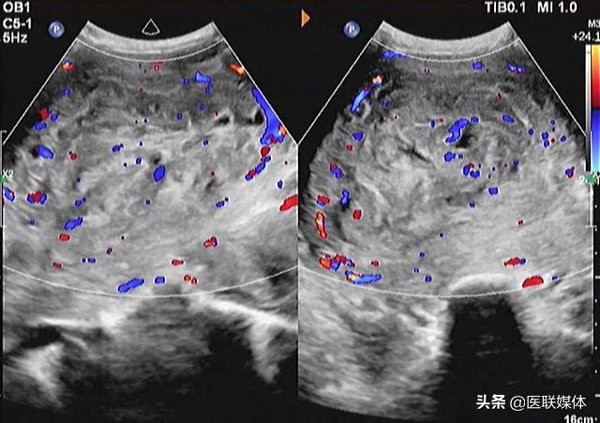

Lo lắng không biết liệu bản thân có thai thật hay không nên cô đã tới bệnh viện kiểm tra. Các bác sĩ nhìn bên ngoài cô Lai trông khá xanh xao, gầy gò, riêng phần bụng thì nhô cao. Kiểm tra siêu âm phát hiện cô Lai có nhiều khối u xơ tử cung lớn đã chạm tới rìa trên của rốn, khối u lớn nhất khoảng 11cm, có khối u khoảng 7cm.

Siêu âm cho thấy có nhiều khối u to, nhỏ khác nhau trong tử cung của cô Lai.